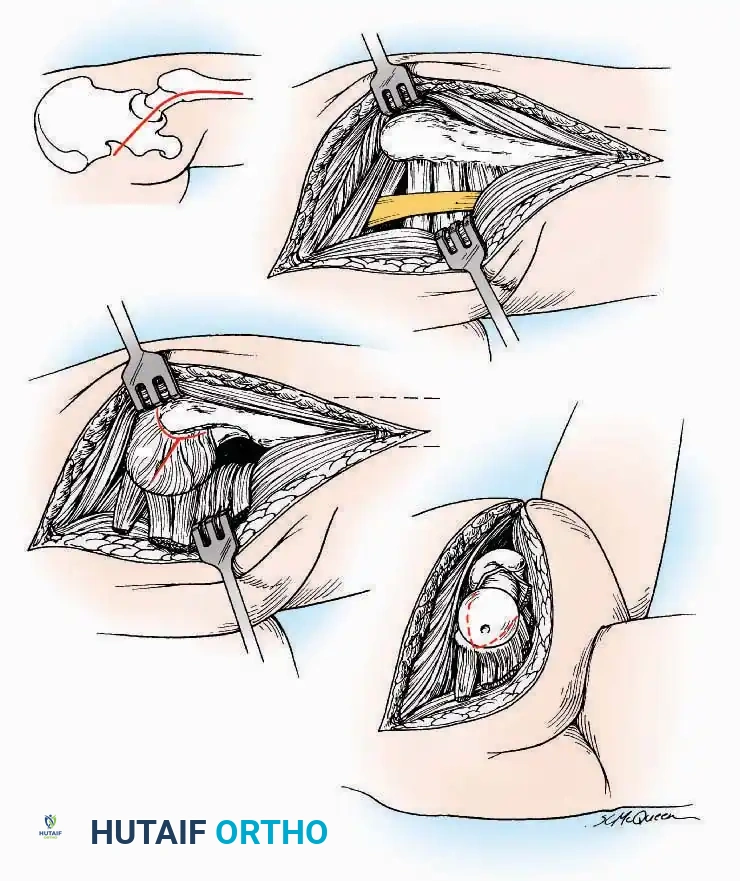

Kocher Approach (Curved L)

Indications: Complete excision of the calcaneus (calcanectomy) for malignant tumors or recalcitrant osteomyelitis.

Surgical Technique:

* Incision: Incise the skin over the medial border of the Achilles tendon, starting 7.5 cm proximal to the calcaneal tuberosity. Extend it distally to the inferoposterior aspect of the tuberosity, curve it transversely around the posterior heel, and continue distally along the lateral surface of the foot to the tuberosity of the fifth metatarsal.

* Deep Dissection: Divide the Achilles tendon directly at its insertion and carry the dissection down to the bone.

* Enucleation: To reach the superior surface, free all tissues beneath the severed Achilles tendon. The calcaneus can then be enucleated subperiosteally or extraperiosteally depending on the oncologic or infectious margins required.